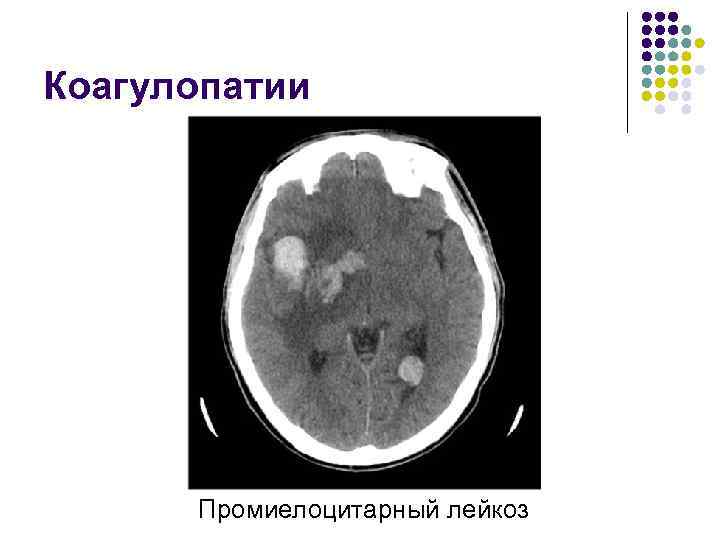

Коагулопатии l l Нарушение свертываемости крови Большая группа заболеваний, включающая в себя прием препаратов, изменяющих свойства крови, тромбоцитопении, опухоли, тромбоцитопеническую пурпуру и другие

Коагулопатии Промиелоцитарный лейкоз